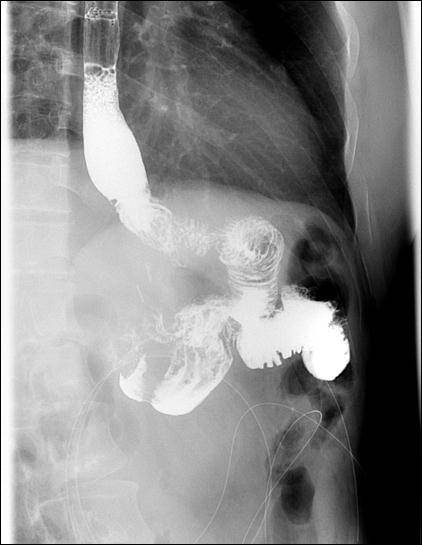

文章图片

双通道吻合术后造影表现